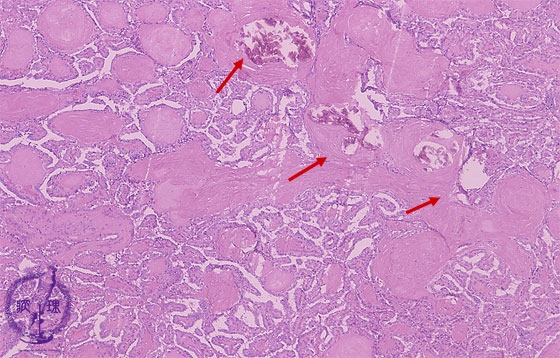

- ★(8)Papillary carcinoma of the thyroid

Microscopic findings (HE stain, low power). Papillary structures of tumor cells and calcification (arrows)